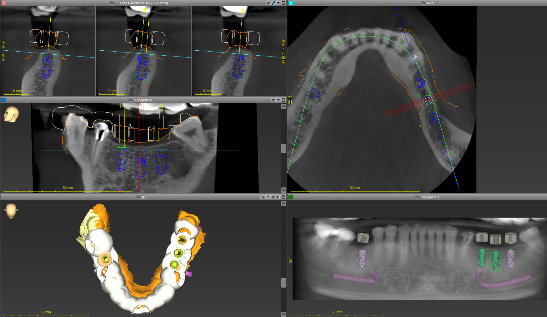

デジタルプランニング

取得したデータをもとに、AIとデジタルソフトでシミュレーションを行います。

骨量・神経位置・審美ラインを正確に把握し、最適なインプラント位置を設計します。

銀座ONE式では、骨造成を基本的に行わず、最小限の侵襲で設計します。

全てデジタル設計による高精度サージカルガイドを使用します。